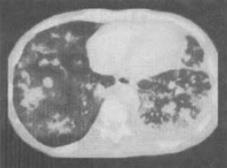

患者男,27岁,干咳,呼吸困难半月余,有艾滋病病史半年余,结合CT检查,最可能的诊断是()。

A、粟粒型肺结核

B、弥漫型肺癌

C、间质性肺炎

D、矽肺

E、卡波济肉瘤

E